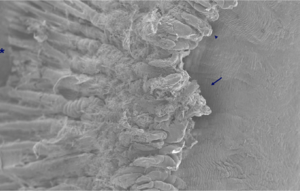

For TSCPC, the common teaching is to start with 1.75-W power and 2.0 -s duration (3.5 J per application); adjust power downward or upward in 0.25-W increments according to whether there are excessive tissue “pops” (Figure 1, evidence of boiling of intracellular water and aqueous) during applications. Eyes with darker pigmentation require slightly lower power and energy per application to obtain equivalent results. With this technique, occasional “pops” will occur. If they occur with every application, the power is too high and should be reduced. Consider lengthening the duration of the laser applications at lower power.